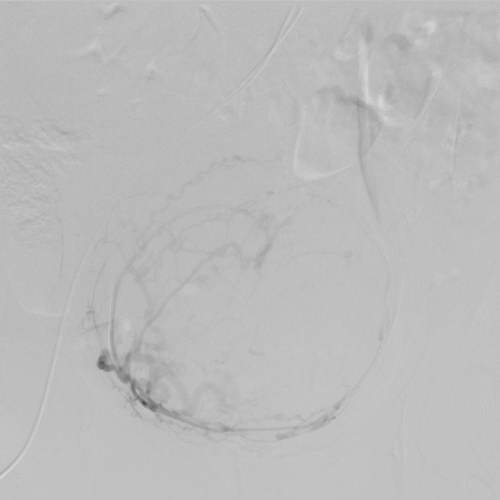

2014 թ. սեպտեմբերի15-ին «Էրեբունի» բժշկական կենտրոնում հերթական բացառիկ վիրահատությունն է անցկացվել՝ արգանդային զարկերակների էմբոլիզացիա՝ արգանդի միոմայի պատճառով: Այս էնդովասկուլյար միջամտությունը միոմայի բուժման արմատական մեթոդներից է:

Վիրահատության տևողությունը 30-40 րոպե է: Վիրահատության էությունը երկու արգանդային զարկերակների էմբոլիզացիա կատարելն է՝ չխախտելով արյան շրջանառությունն արգանդում: Այն նվազագույն միջամտություն պահանջող և քիչ վնասվածքներ հարուցող վիրահատություն է, որն իրականացվում է տեղային անզգայացմամբ: Վիրահատությունը հնարավորություն է ընձեռում խուսափել հիստեէկտոմիայից (արգանդի հեռացումից), առավել ևս, երբ կինը դեռ վերարտադրողական տարիքում է գտնվում: Այսպիսի վիրահատություններ կարելի է անցկացնել ինչպես եզակի միոմայի, այնպես էլ ցանկացած տեղայնացման արգանդի միոմատոզի ժամանակ: